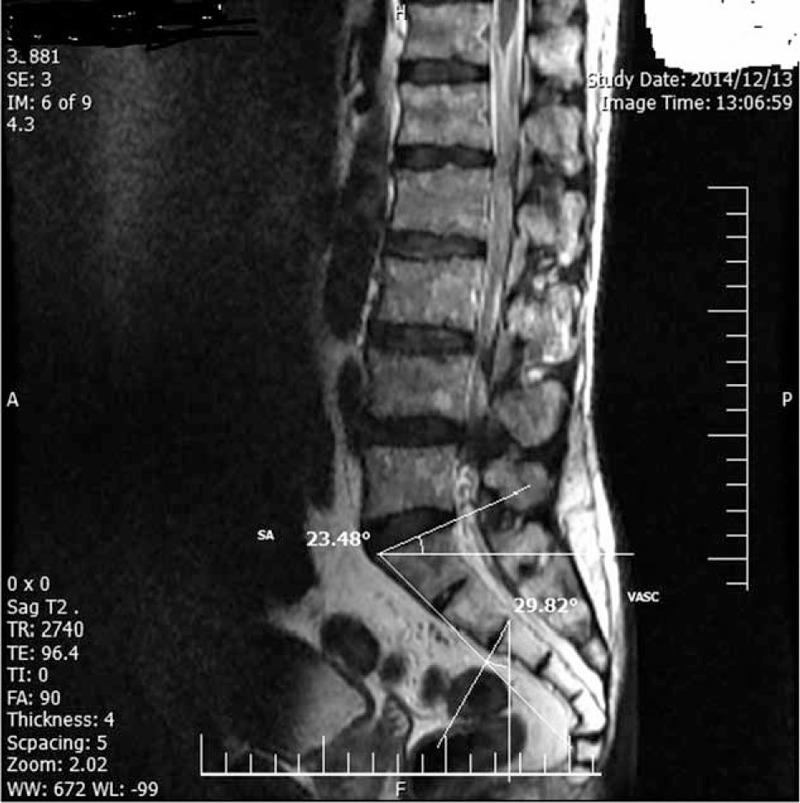

The purpose of this study is to determine the reliability and validity of a goniometric measurement of the vertical angle of the sacrum and sacral angle (SA), and their relationships to lumbar degeneration.A herniated lumbar disc is one of the most frequent medical issues. Investigators in a number of studies have reported associated risk factors for prevalent disc degeneration. Atypical lumbosacral angles and curvature are thought to contribute to the degradation of the spine by many researchers. This study analyzed 360 patients referred to our clinic from 2013 to 2015 due to low back pain. A cross-sectional case-control study was designed in order to compare the sagittal alignment of the lumbosacral area in 3 groups of patients suffering from LBP. A total 120 patients were in a control group with a normal lumbar magnetic resonance imaging (MRI), 120 patients had lumbar disk herniation (LDH), and 120 patients had spinal stenosis. From the sagittal plan of lumbar MRI, SA and vertical angle of sacral curvature (VASC) were determined and then analyzed.The means of VASC in these groups were: 38.98 (SD: 6.36 ± 0.58), 40.89 (SD: 7.69 ± 0.69), and 40.54 (SD: 7.13 ± 0.92), respectively (P = 0.089). Moreover, studies of SA in 3 groups showed that the means of SA were: 39.30 (SD: 6.69 ± 0.63), 40.52 (SD: 7.47 ± 0.65), and 35.63 (SD: 6.07 ± 0.79), respectively. Relation between SA and spinal stenosis was just statistically significant (P ≤ 0.05).One significant limitation of our study is the lack of standing MRI for increased accuracy of measurement. However, we were reluctant to give patients needless exposure to radiation from conventional X-ray, and instead used MRI scans. We did not find any significant correlation between the VASC and LDH in lumbar MRI. Also, SA is not an independent risk factor for LDH in men and women. We suggested that there are several biomechanical factors involved in LDH.

本研究的目的是确定测量骶骨垂直角和骶骨角(SA)的测角法的可靠性和有效性,以及它们与腰椎退变的关系。腰椎间盘突出症是最常见的医学问题之一。多项研究的调查人员报告了普遍存在的椎间盘退变的相关危险因素。许多研究人员认为,非典型腰骶角和曲率会导致脊柱退变。本研究分析了2013年至2015年因腰痛转诊至我院门诊的360例患者。设计了一项横断面病例对照研究,以比较3组腰痛患者腰骶部的矢状位排列。对照组共有120例患者腰椎磁共振成像(MRI)正常,120例患者患有腰椎间盘突出症(LDH),120例患者患有椎管狭窄。从腰椎MRI的矢状面确定并分析SA和骶骨曲率垂直角(VASC)。这些组中VASC的平均值分别为:38.98(标准差:6.36±0.58)、40.89(标准差:7.69±0.69)和40.54(标准差:7.13±0.92)(P = 0.089)。此外,3组中SA的研究表明,SA的平均值分别为:39.30(标准差:6.69±0.63)、40.52(标准差:7.47±0.65)和35.63(标准差:6.07±0.79)。SA与椎管狭窄之间的关系仅具有统计学意义(P≤0.05)。本研究的一个显著局限性是缺乏站立位MRI以提高测量准确性。然而,我们不愿让患者不必要地暴露于传统X射线辐射,而是使用了MRI扫描。我们在腰椎MRI中未发现VASC与LDH之间存在任何显著相关性。此外,SA不是男性和女性LDH的独立危险因素。我们认为LDH涉及多种生物力学因素。